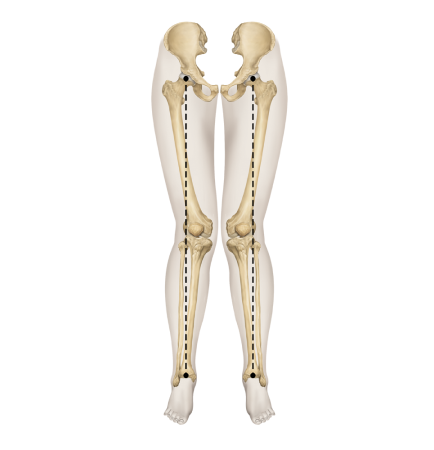

▲ O자 다리

▲ X자 다리

▲ 정상 다리

휜다리의 대표적 유형 2가지

O다리

• 무릎이 외측으로 벌어지면서 다리 축이 변형됨

• 체중부하가 다리 안쪽(내측)에 집중되어 내측 관절의 압력증가로

무릎관절의 퇴행성 변화와 통증을 초래

• 허벅지 안쪽 근육이나 엉덩이 근육이 약화되면 무릎 안정성이 떨어져 내반슬이 악화

X다리

• 무릎이 안쪽으로 모이면서 다리 축이 변형됨

• 체중 부하가 다리 바깥쪽에 집중되어 외측 관절의 압력증가로

무릎 통증, 불안정성, 관절 손상을 유발할 수 있음

• 허벅지 바깥쪽 근육이 과도하게 발달하고 안쪽 근육이 약화되면 외반슬이 진행

휜다리는 단순히 무릎 사이 간격이 벌어진 것이 아닙니다.

무릎 위의 대퇴골과 아래의 정강이뼈가 회전하면서 무릎까지 뒤로 빠지기 때문에 다리사이 간격이 넓어지는 겁니다.